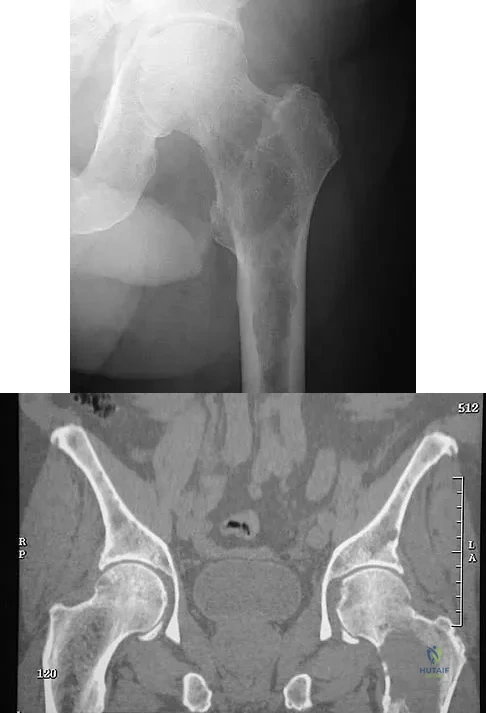

Question 97

Figures 29a and 29b show the AP radiograph and CT scan of a 70-year-old man who has left thigh pain. Serum protein electrophoresis shows a monoclonal gammopathy. Additional radiographs of the femur show other lesions. Management should consist of

Explanation